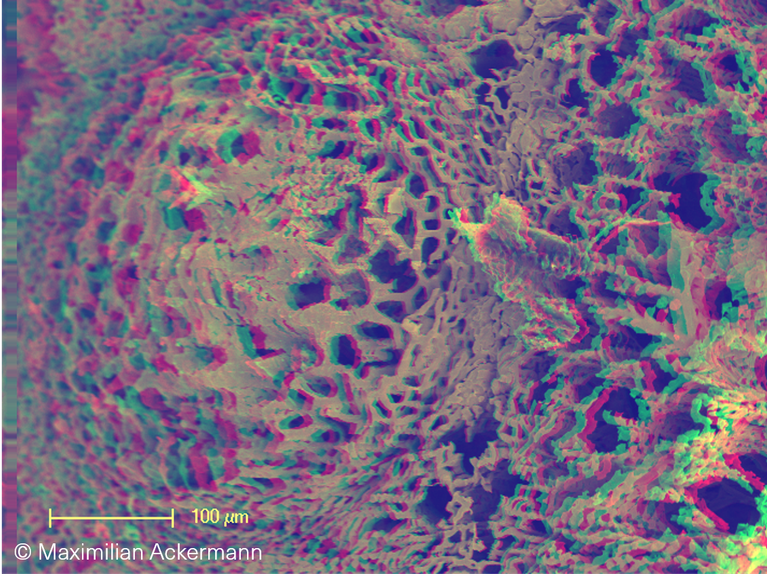

Colon cancer

In contrast, microvascular architecture in colon adenocarcinoma is characterized by  the chaotic arrangement of abnormal, tortous tumor blood vessels.